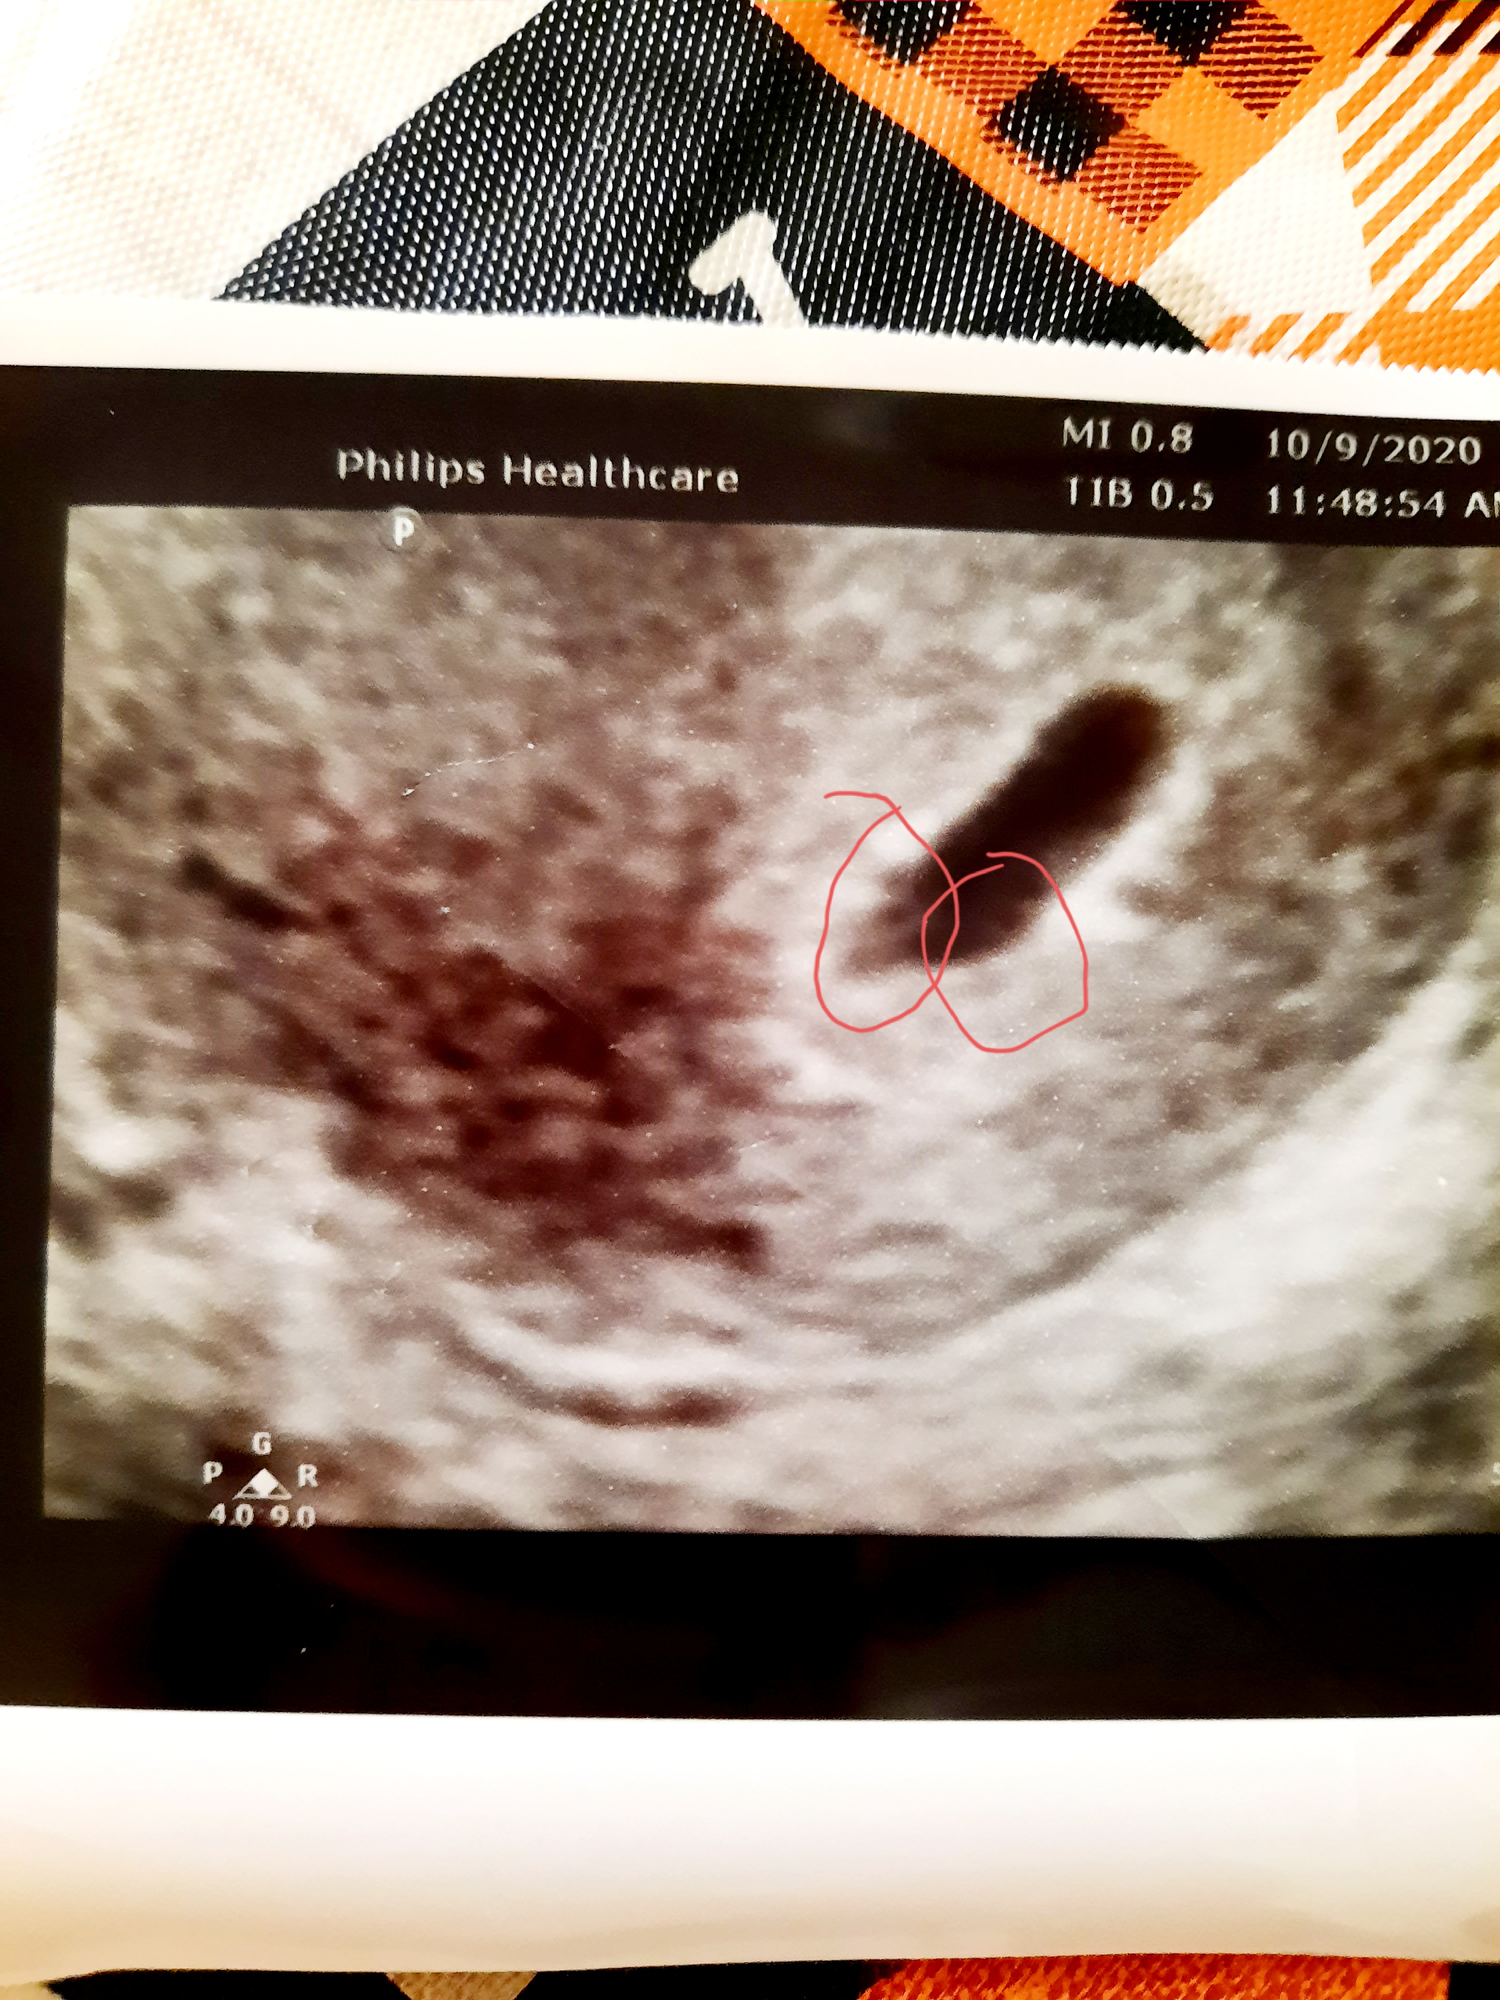

• I need to come back in 2 weeks for a clearer ultrasound. He said he a saw a yolk sac and obviously the gestational sac but nothing else. Im probably hanging onto hope haha but I think I potentially see 2 yolk sacs. The doc said he wouldn't rule out twins  at this point until next ultrasound.  What do you think,  you see what I see??

• I replied under the multiples post. I think it's too early to tell at this point. It sounds like you really want twins. I know I do. I have a scan 10/20 which will be 6 and a half weeks. By then should be able to see how many, maybe even hear heartbeats. By your next scan you'll definitely know what's going on. Just hang in there and keep us updated!

I was confused bc my first scan at 4.5 weeks showed only one sac, like your pic, but now we clearly saw two. These are di/di twins, the lowest risk kind, with separate placentas.